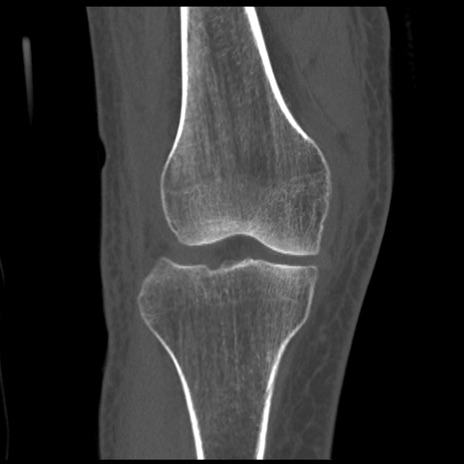

症例28 右膝関節CT(冠状断像)

右膝関節CT